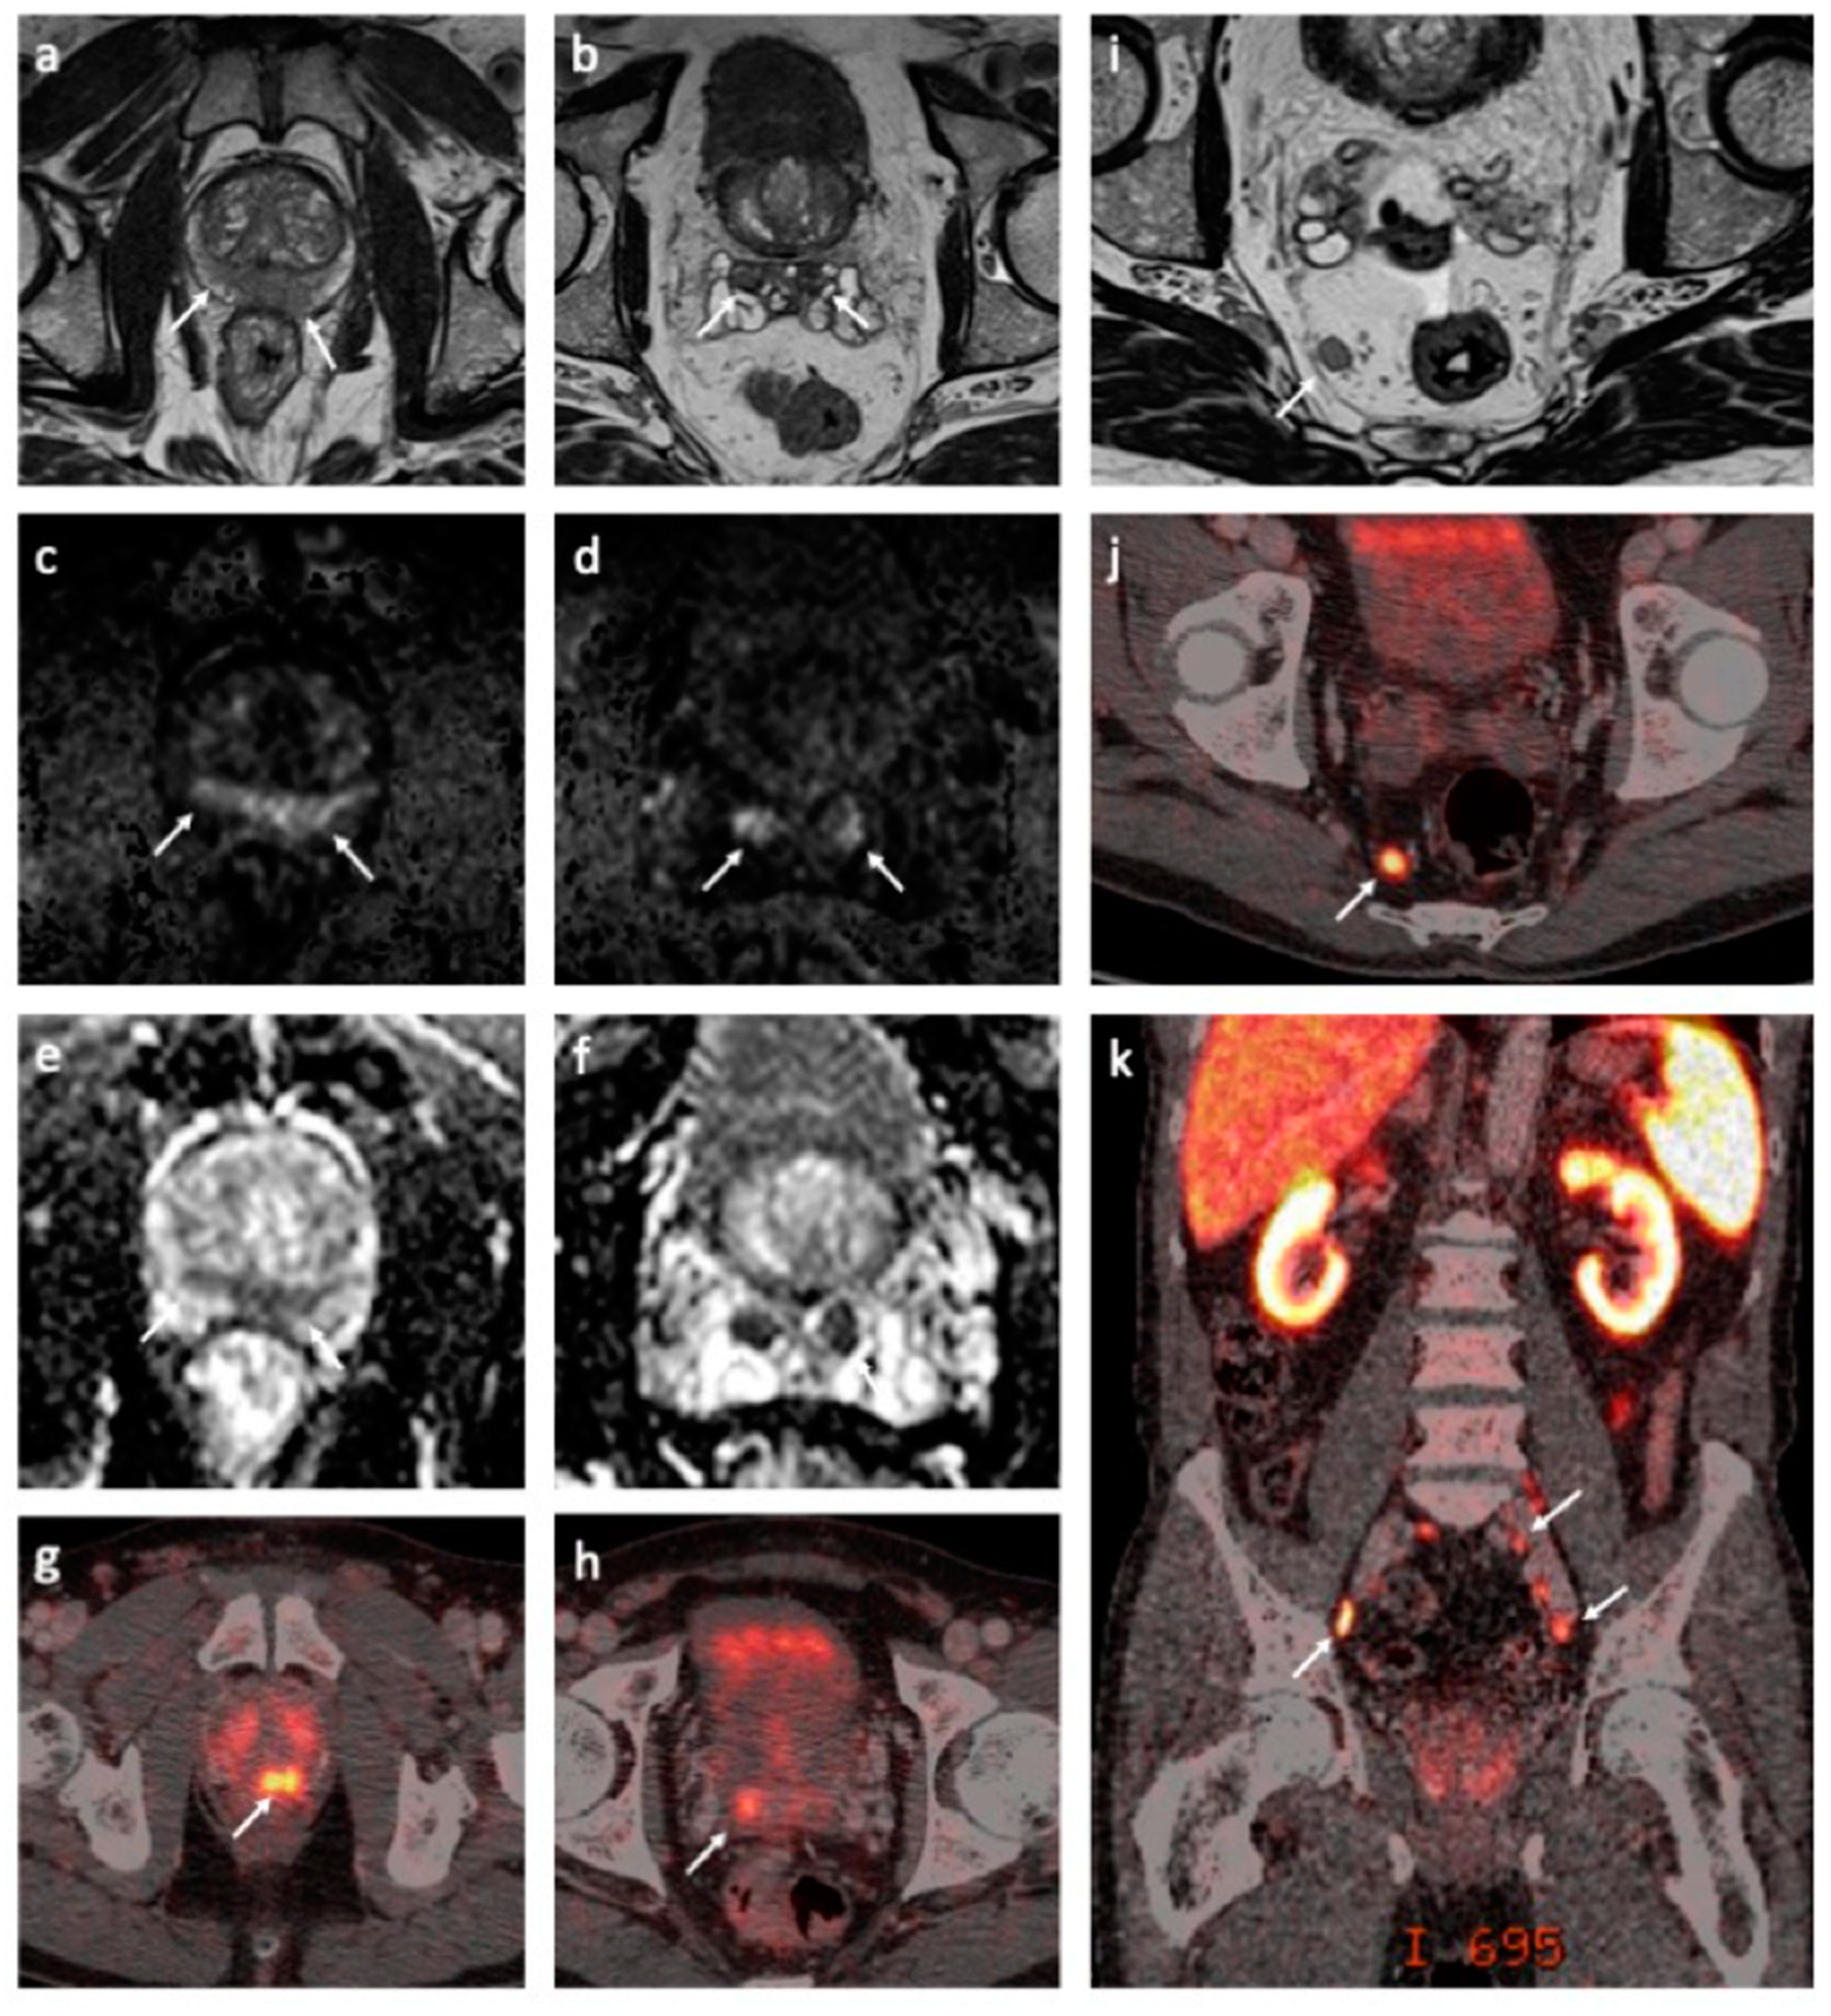

5.2. MRI Findings